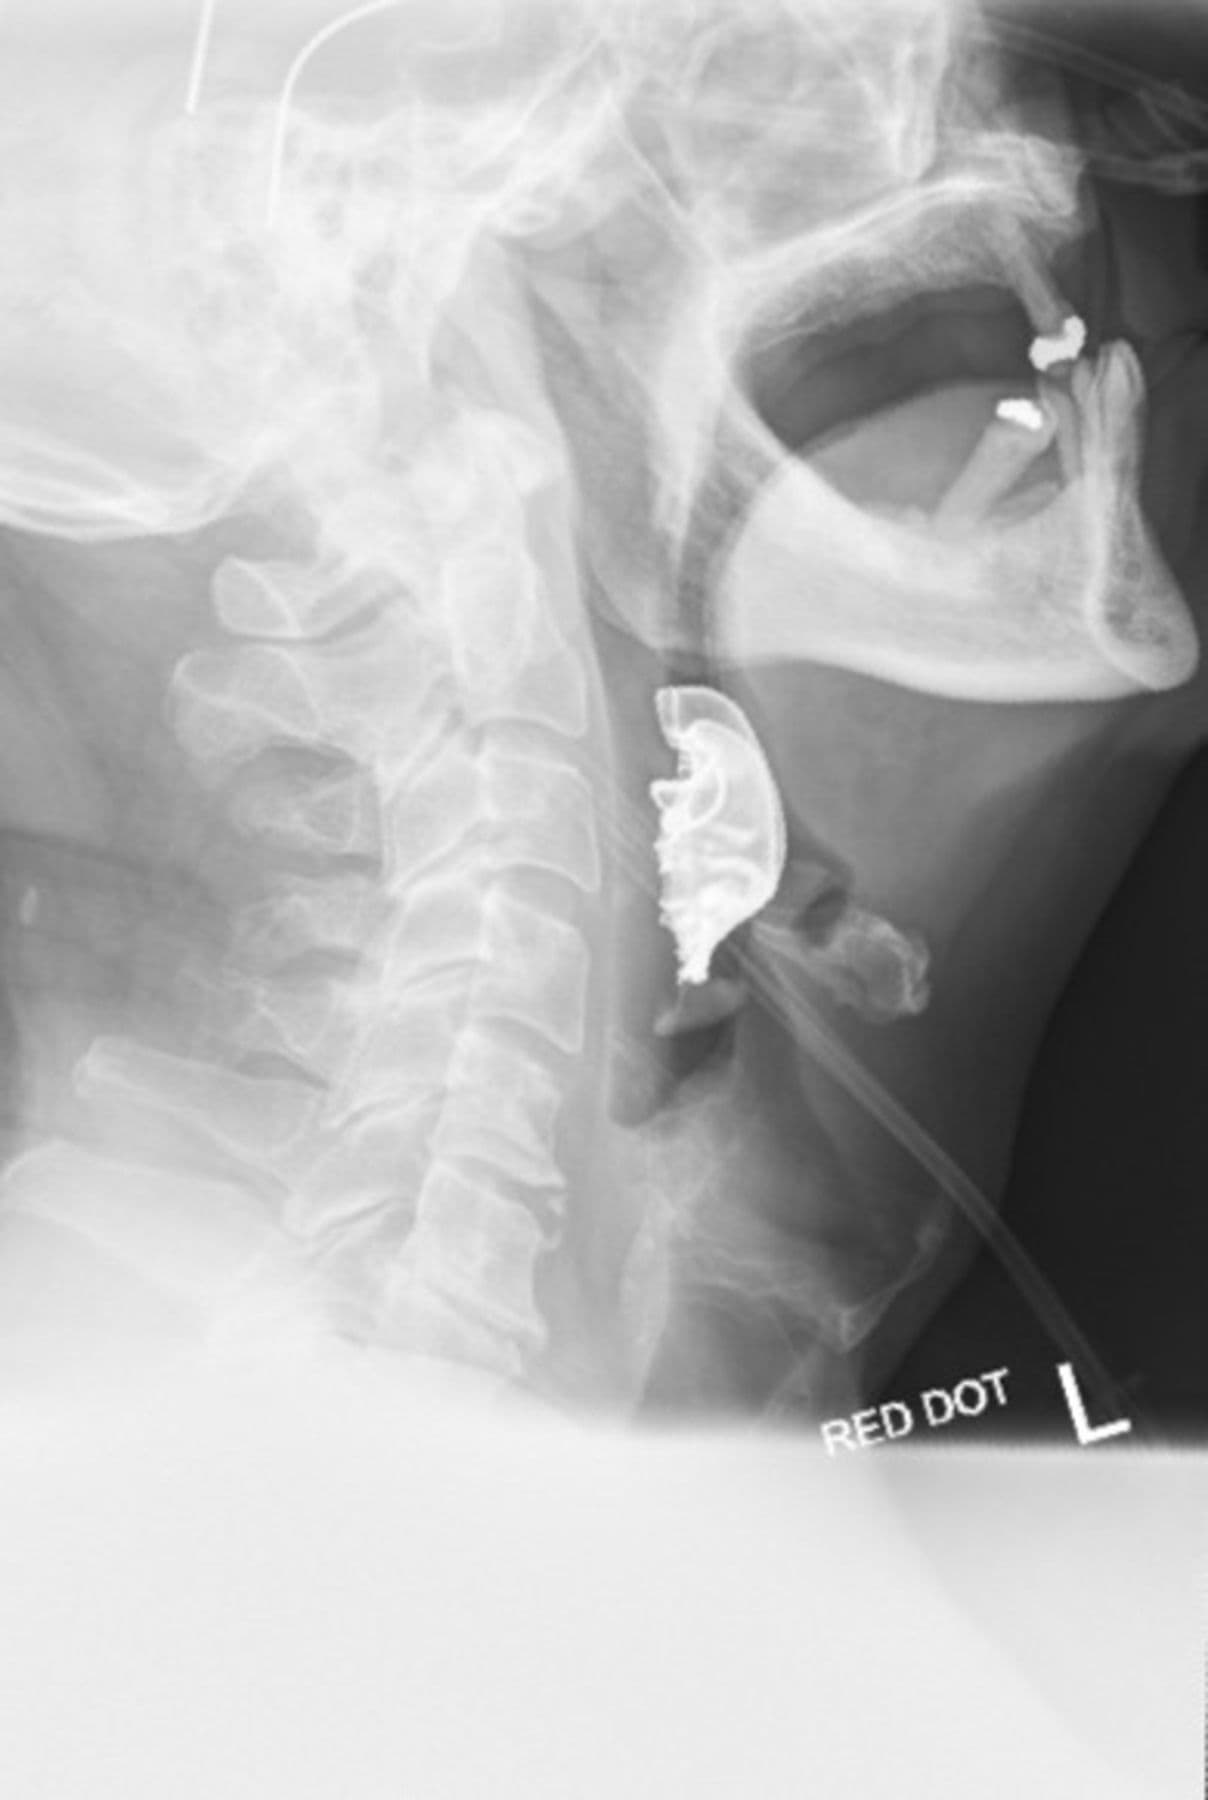

El hombre f ue a la sala de emergencias porque le costaba tragar y tosía sangre. Los médicos ordenaron una radiografía del tórax y como sospechaban que se trataba de una infección respiratoria lo mandaron a casa con una dotación de antibióticos. Pensaron que el problema era un efecto secundario de la intubación durante la operación.

Pero los síntomas se agudizaron y el paciente tuvo que volver al hospital, pues tenía dificultad para respirar, no podía ingerir alimentos y el sangrado continuaba.

Al revisar la garganta, los médicos detectaron un objeto extraño que tapabas sus cuerdas vocales. Una nueva radiografía reveló el origen de su malestar: un puente metálico y tres dientes postizos se habían alojado en la parte superior de su garganta.